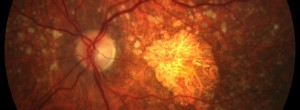

Ensayo clínico OPH2005: Eficacia y seguridad de Zimura en el tratamiento de la enfermedad de Stargardt